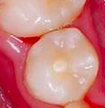

在恆牙萌發時,當牙齒根尖還沒有完全閉合時,有蛀牙、外傷、或是牙齒結構異常(如亞洲人種小臼齒常見牙中牙的結構,如下圖臨床照片),造成牙髓的感染,因而影響牙根繼續發育,使牙齒結構弱化。

牙根成形術能保留殘存牙髓的活性(須經根管專科醫師的評估),並消除牙根感染,使牙根繼續發育、牙齒管壁變厚,齒質結構強化直到牙齒的生長潛能完全發揮。